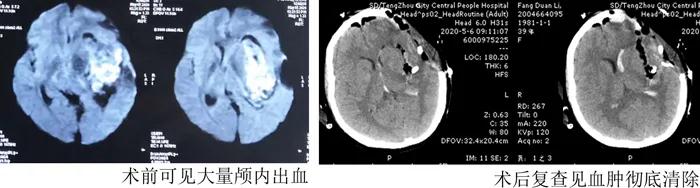

雖然手術(shù)順利,但患者暫時仍未脫離生命危險,決定將患者轉(zhuǎn)入重癥監(jiān)護室繼續(xù)救治。早已在監(jiān)護室等候的朱思良醫(yī)生和產(chǎn)科顏曉華大夫迅速對產(chǎn)婦進行了全面細致的評估,并制定了周密的治療方案。在隨后5天的精心治療和護理中,產(chǎn)婦逐漸恢復(fù)了意識,肢體活動部分恢復(fù),復(fù)查顱腦CT見血腫完全清除。5月10號母親節(jié),在這個特殊的日子,患者脫離生命危險轉(zhuǎn)到普通病房,終于見到了焦急等待的丈夫和轉(zhuǎn)危為安的女兒!